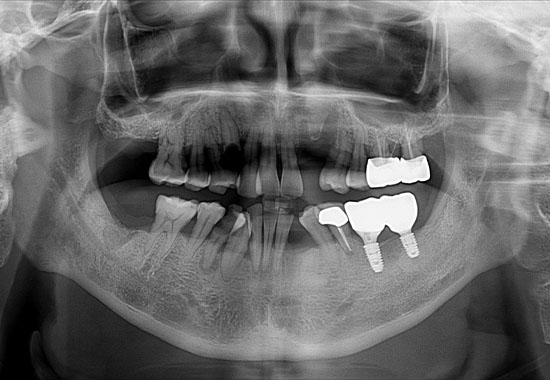

BEFORE

AFTER

- 식립 개수 : 13개 (상악 6개 하악 7개), 크라운 15개

- 수술 내용 : 양쪽상악동 거상